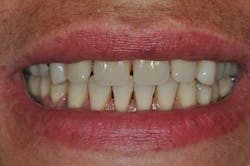

Fig. 2: Anterior teeth relationships prior to treatment

- Provisional acrylic removable partial denture placement after the extractions of the upper teeth. It serves as a functional and esthetic test for the rest of the treatment.

Figs. 3a, b, and c: Extraction of the upper incisors and maxillary removable acrylic placement